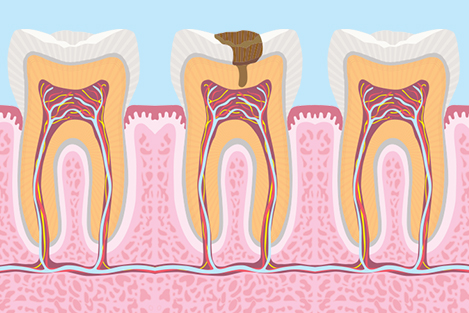

4. RCT(Root Canal Treatment)

A root canal is a treatment to repair and save a badly damaged or infected tooth. The procedure involves removing the damaged area of the tooth (the pulp), cleaning and disinfecting it and then filling and sealing it. The common causes affecting the pulp are a cracked tooth, a deep cavity, repeated dental treatment to the tooth or trauma. The term "root canal" comes from cleaning of the canals inside the tooth's root.

Endodontic therapy or root canal therapy is a sequence of treatment for the infected pulp of a tooth which results in the elimination of infection and the protection of the decontaminated tooth from future microbial invasion. Root canals, and their associated pulp chamber, are the physical hollows within a tooth that are naturally inhabited by nerve tissue, blood vessels and other cellularentities. Together, these items constitute the dental pulp.Endodontic therapy involves the removal of these structures, the subsequent shaping, cleaning, and decontamination of the hollows with small files and irrigating solutions, and the obturation (filling) of the decontaminated canals. Filling of the cleaned and decontaminated canals is done with an inert filling such as gutta-percha and typically a eugenol-based cement.Epoxy resin is employed to bind gutta-percha in some root canal procedures.Endodontics includes both primary and secondary endodontic treatments as well as periradicular surgery which is generally used for teeth that still have potential for salvage.